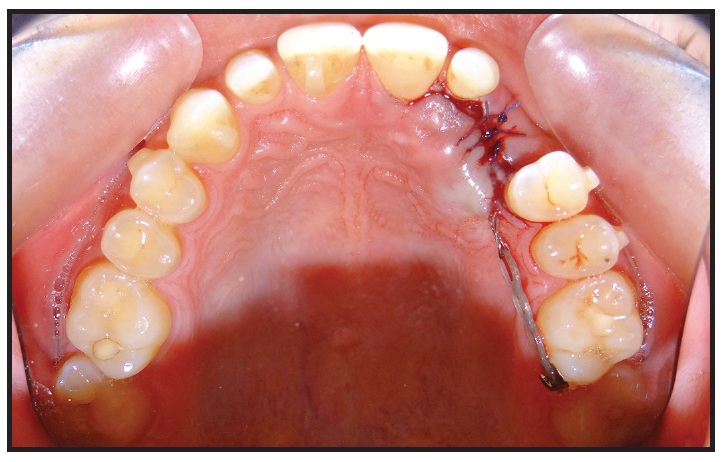

Case 1: Applying an Extrusive Traction Force

A 22-year-old female was referred by her general dentist for treatment of retained upper deciduous canines (Fig. 1A). She had a mildly convex soft-tissue profile, excessive lower anterior facial height, and an obtuse nasolabial angle. The smile arc was consonant, with 90% gingival display, but some lip incompetence was noted. The lower midline was deviated to the left of the facial midline. The overjet was 4mm, and the overbite less than 1mm. Mild Class II molar relationships were present on both sides.

Fig. 1 Case 1. 22-year-old female patient with bilaterally impacted upper canines before treatment (continued in next image).

The panoramic radiograph showed that both upper canines were impacted and slightly overlapping the roots of the lateral incisors. Cone-beam computed tomography (CBCT) evaluation revealed a palatal position of the left canine and a mid-crestal position of the right canine (Fig. 1B).

Fig. 1 (cont.) Case 1. 22-year-old female patient with bilaterally impacted upper canines before treatment.

At the beginning of treatment, the upper deciduous canines were extracted and temporarily replaced with pontics added to the aligner trays by filling the labial aspects with composite (see box).

After the attachments were bonded, the patient was referred for surgical exposure of the canines. An open-exposure procedure was performed on the upper left canine, and traction began immediately. To move the canine distally, away from the lateral-incisor root, an elastomeric module was tied from a ligature wire extending out of the tissue to a lingual button on the first molar. Two months later, the right canine was exposed, and the same treatment protocol was followed.